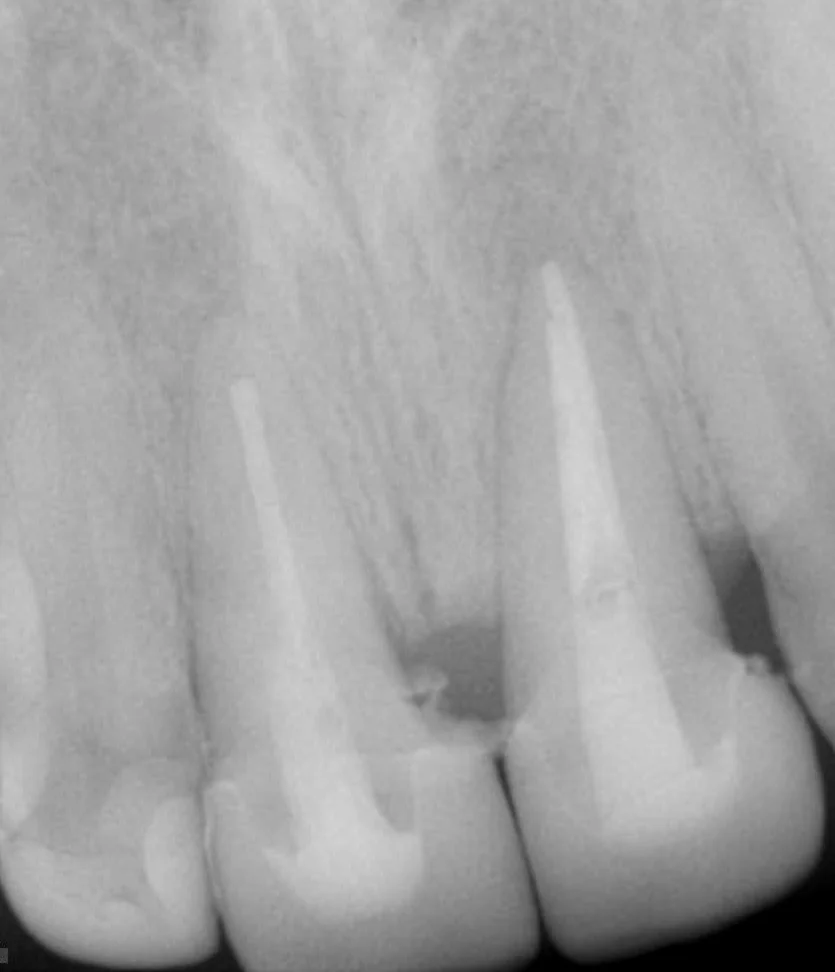

Surgical repositioning of teeth

Initial clinical presentation with CC of "Can you cement back my tooth?"

Removed post and surgically repositioned for 2 mm ferrule

Crowns delivered after 12 weeks of the surgical repositioning. Happy patient.